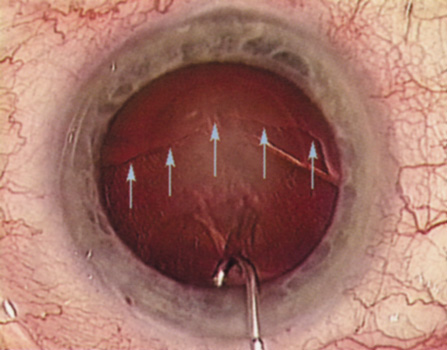

Fig. 12. Hydrodissection, performed subincisionally with a 27-gauge J-cannula, produces a cleavage plane between the capsule and the cortex. The small blue arrows indicate the advancing fluid wave.

Hydrodissection can be performed after the surgeon has successfully completed capsulorrhexis.97 If the capsulorrhexis is not intact, fluid forced around the interior of the capsule may cause the bag to splay open. With capsulorrhexis, hydrodissection is a safe and extremely useful maneuver. Hydrodissection can be thought of as two maneuvers: hydrodelineation and cortical cleaving hydrodissection. By placing a 27-gauge cannula on a syringe filled with balanced saline solution (BSS), the surgeon can direct fluid beneath the residual anterior capsular rim to create a cleavage plane. Depending on the direction the fluid wave takes, different lamellae of the cataract will be separated. Hydrodelineation is the term used when the cleavage plane separates the adult nucleus from the fetal nucleus or the adult nucleus from the more peripheral epinucleus. Hydrodelineation often results in the characteristic golden ring sign (Fig. 11). Cortical cleavage occurs when the cortex is separated from the capsular bag (Fig. 12). Finding the cortical cleavage plane may be facilitated by gently lifting the capsular margin away from the cortex with the BSS cannula before injecting. Several small bursts of fluid allow the surgeon to monitor progress of the fluid wave. When dealing with a soft nucleus, the authors strive to perform true cortical cleaving hydrodissection. For a hard nucleus, hydrodelineation allows manipulation of less of the nuclear bulk, although the remaining epinuclear shell must be addressed in an additional step. Hydrodelineation is particularly useful if the nucleus is not freely mobile after cortical cleaving hydrodissection.